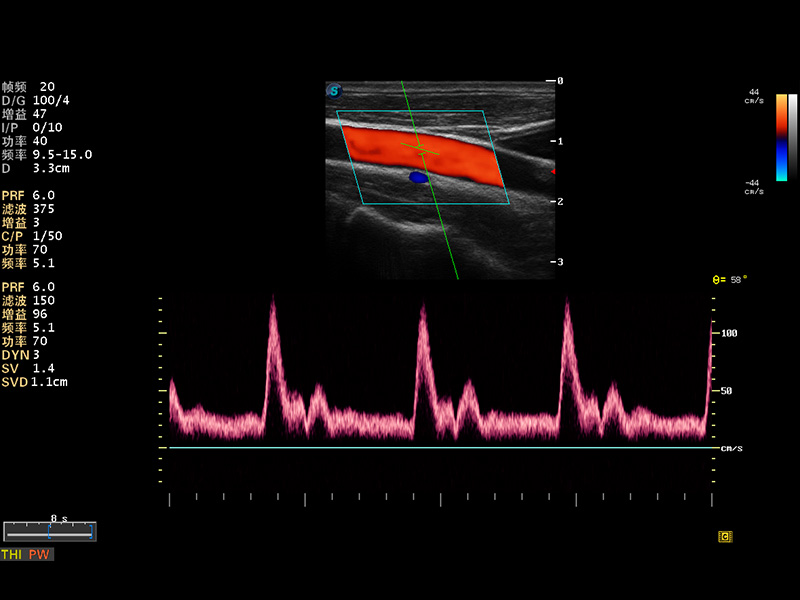

S8 EXP便携式彩色多普勒超声诊断仪是亚星官网研发的高端全身应用型便携彩超。高通道的VIS平台融合可视化(Visual)、智能化(Intelligent)和人性化(Smart)的特点,配以亚星官网自主研发生产的探头大家族,使您能够快速、准确的获得病人信息,提高工作效率的同时减轻疲劳。

μ-Scan微米成像